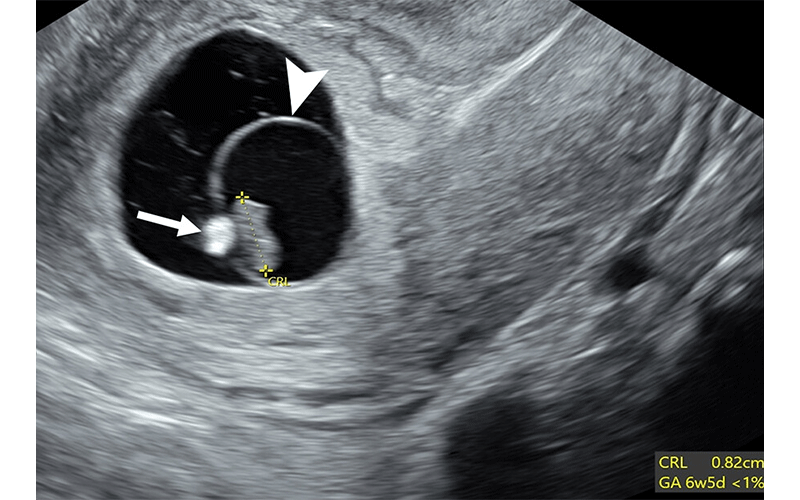

Poor prognosticators: calcified yolk sac and expanded amnion sign. Transvaginal sagittal grayscale US image in a 27-year-old pregnant patient shows an 8-mm embryo (calipers) without cardiac activity (M-mode not shown) sufficient for the interpretation of diagnostic of early pregnancy loss (EPL). Additional poor prognosticators include a calcified yolk sac (arrow) and an enlarged amniotic cavity (arrowhead) relative to the crown-rump length (CRL) of the embryo, called the expanded amnion sign. These additional observations, on their own, are only concerning for EPL. GA = gestational age.